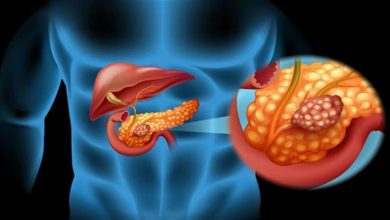

عدو خفي على سفرتك.. أكلة تدمر البنكرياس ودماغك والكوليسترول

كتبت- أسماء مرسي: الوجبات السريعة من الأطعمة الأساسية في حياة الكثيرين، نظرا لسرعتها وسهولة الحصول عليها، ولكن هل تعلم ما…